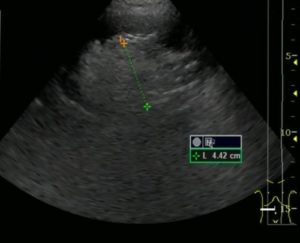

В основе консервативного лечения лежит тактика наблюдения. Врач регулярно назначает больному обследования, позволяющие следить за ростом и развитием липомы в динамике. Пока размер новообразования не превышает 4 см, необходимости в оперативном лечении нет.

В случаях, когда опухоль имеет размеры до четырех сантиметров, функция пораженного органа сохранена и в наличие не прогрессивный рост без присутствия жалоб и осложнений выбирают консервативное ведение таких больных. Она заключается в динамическом наблюдении и проведении обследования один раз в год.

Она основывается на методах врачебного контроля, что позволяет отслеживать динамику развития и роста опухоли. Обязательно проведение КТ и УЗИ не меньше одного раза в год. При диаметре опухоли менее 4 см вмешательства хирурга не требуется.

Допустимые размеры новообразования до 4 см. При размерах до 4 см болезнь проходит обычно бессимптомно, не оказывая никакого воздействия. При опухоли более 5 см симптоматика более проявлена.

Характер терапии определяется в зависимости от параметров заболевания, динамики развития. При величине менее 400 мм врач-нефролог наблюдает за состоянием пациента, никакие терапевтические процедуры не назначаются. Рекомендуют наблюдение на УЗИ и КТ раз в 1 год.